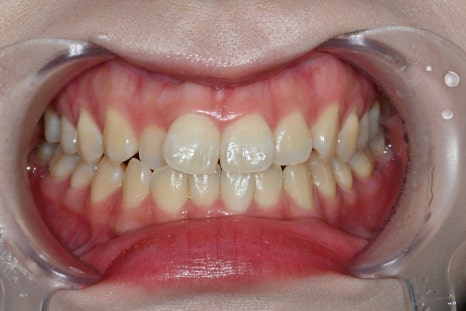

<before>

<after>

The changes after laminate are not simple.

Improved smile line

Changed facial impression

Natural appearance in photos

Increased confidence

All of these changes appear together.

The patient also responded,

“It looks natural without feeling like I had laminate done.”